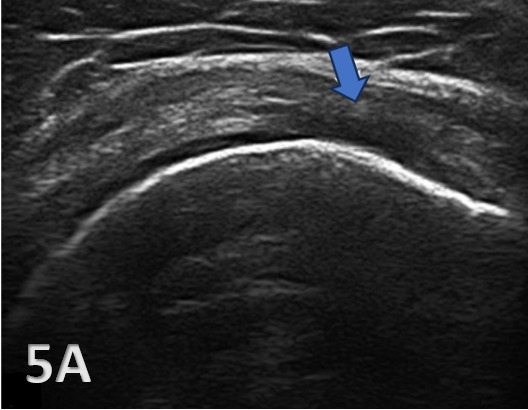

Transverse Scans: Begin with transverse scans to identify the spine of the scapula and follow the muscle belly towards its insertion on the humerus. The transducer is transversely placed inferiorly and slightly laterally from the scapular spine. Passive internal and external rotation of the patient’s arm may be helpful in visualization of the tendon. The infraspinatus tendon appears as a beak-shaped soft-tissue structure that progressively thins as it approaches its attachment to the posterior aspect of the greater tuberosity.6 Additional structures seen at this level are the posterior glenoid labrum, imaged as a hyperechoic triangular structure and the hypoechoic articular cartilage of the humerus.

Ultrasound imaging of the infraspinatus must be carefully interpreted. Normal anatomy appears as a fibrillar pattern with uniform echotexture. Pathological findings may include:

Tears: Full-thickness or partial-thickness tears are displayed as hypoechoic or anechoic (absence of echoes) defects within the tendon. Additionally, they may be identified by discontinuities in the tendon fibers.